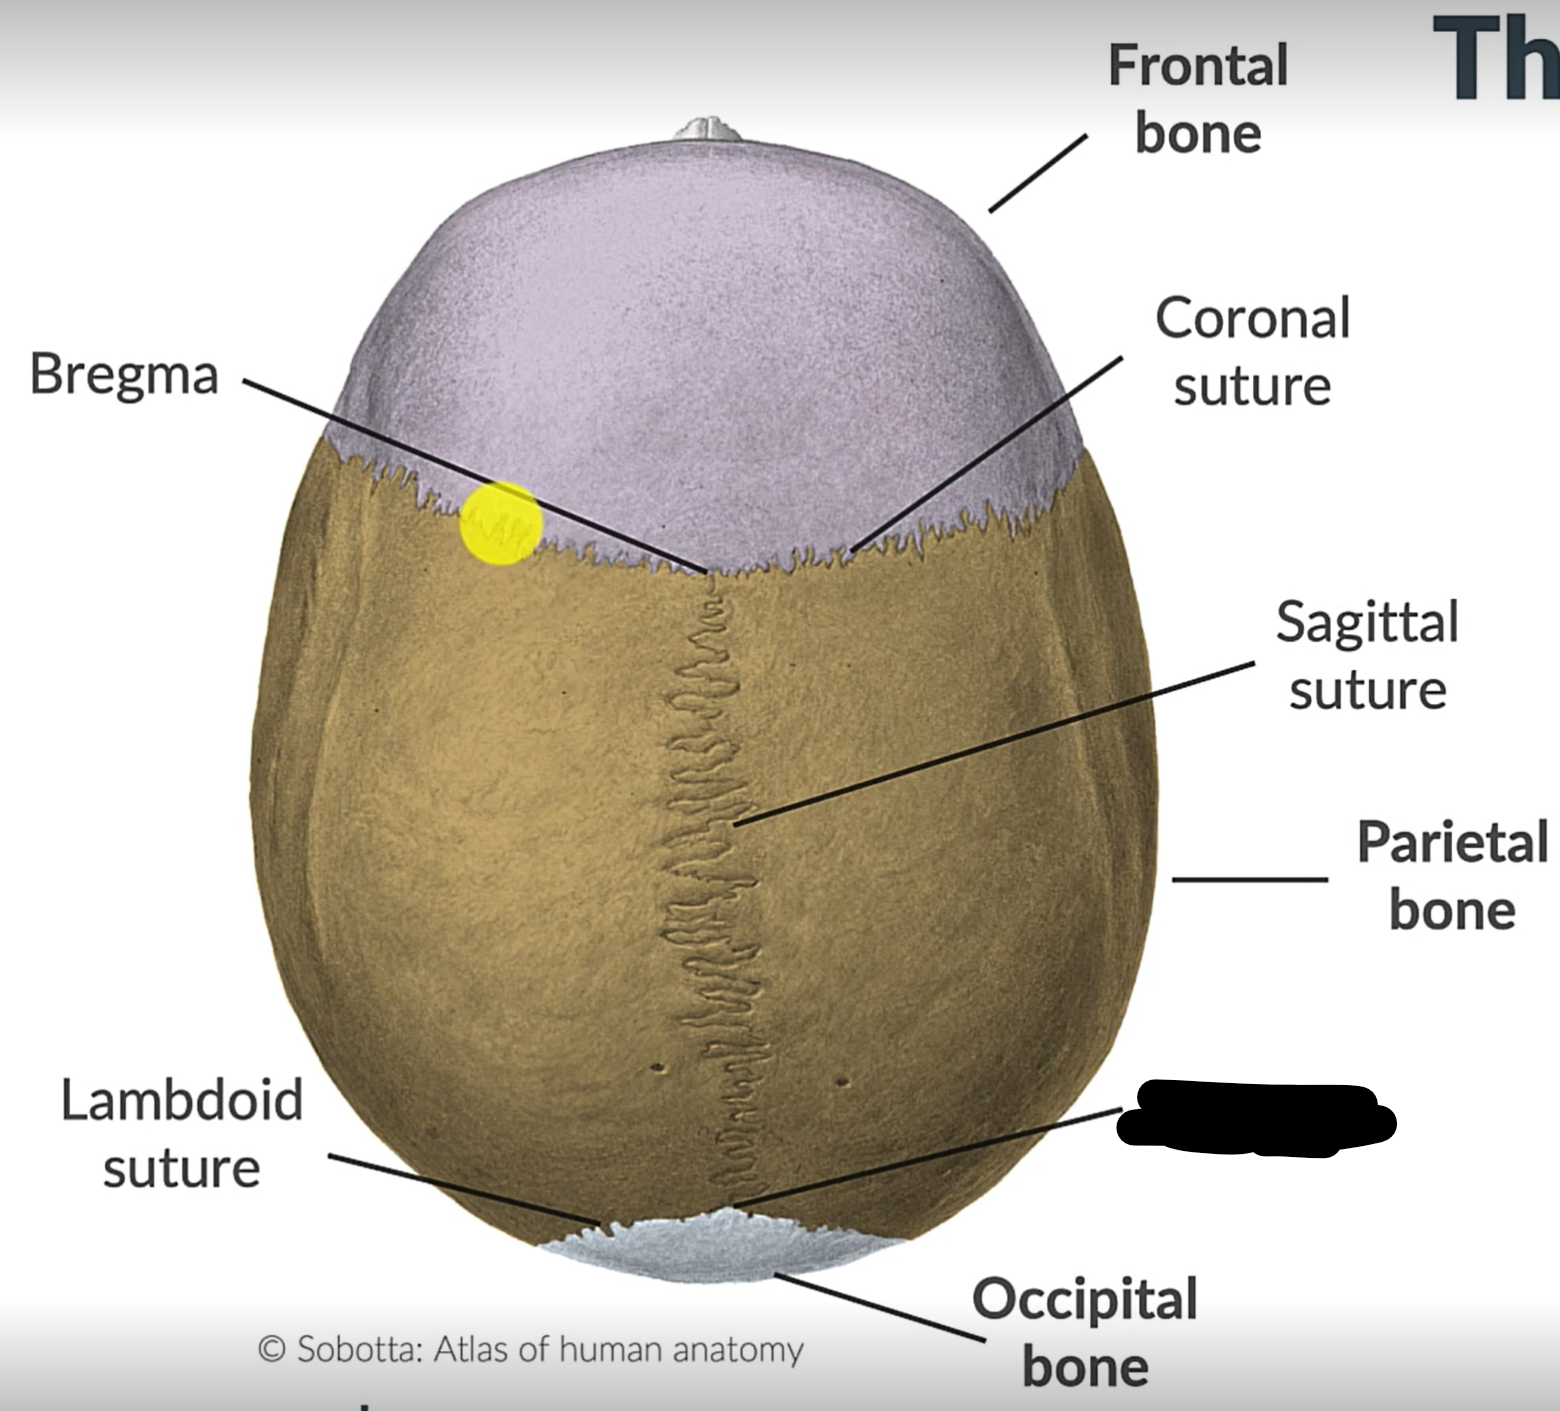

What are the 4 cranial sutures and what do they separate?

Lambdoid - separates occipital from parietal and temporal

Sagittal - extends between parietal bones

Coronal - divides frontal and parietal bones

Squamous - either side of cranium, separates temporal and parietal bones

Sagittal suture

Parietal bone

Lambdoid suture

Occipital bone

What is the point where the frontal and parietal bones meet?

Bregma

Lambda